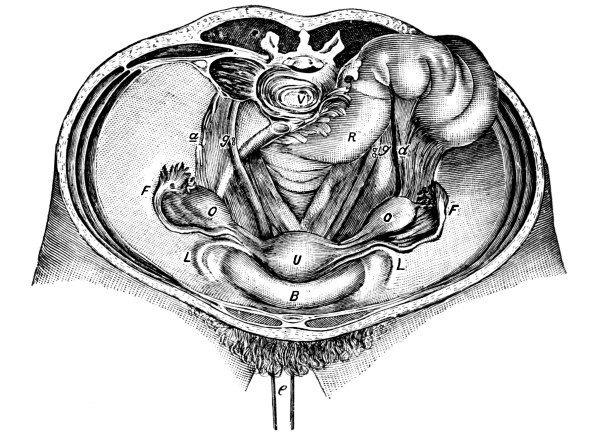

| The Pelvis and the Genital Organs | 161 |

The Pelvis, 161—The Male Generative Organs, 164—The Prostate Gland, 164—The Testes, 165—The Penis, 165—The Female Generative Organs, 165—The Ovaries, 165—The Fallopian Tubes, 166—The Uterus, 167—The Vagina, 168—The External Genitalia in the Female, 169—The Vulva, 169—The Mons Veneris, 169—The Labia Majora, 169—The Labia Minora, 170—The Clitoris, 170—The Meatus Urinarius, 170—The Hymen, 170—The Fourchette, 170—The Perineal Body, 170—The Perineum, 170. |